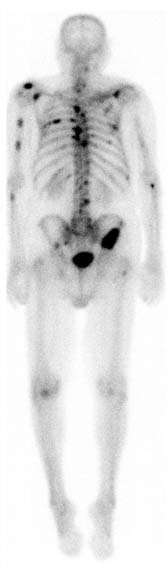

A patient undergoing a SPECT bone scan. The patient lies on a table that slides through a scanner, while two gamma cameras rotate around him. Machine operators typically work remotely from another room, shielded from the radiation being emitted by the patient.